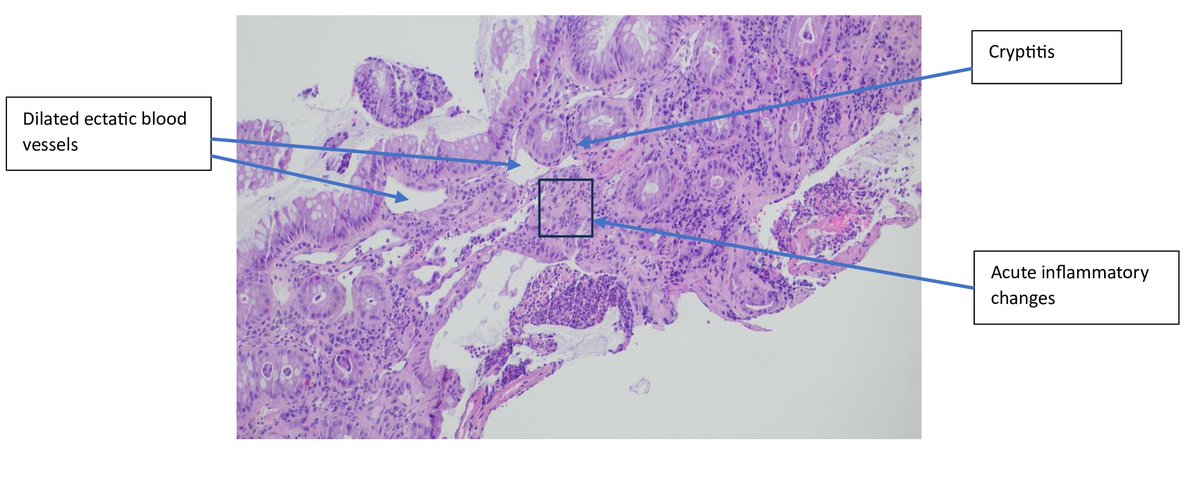

A 45-year-old woman with cervical carcinoma underwent radiation therapy and subsequently developed radiation colitis. Histopathology reveals mucosal atrophy, crypt distortion, and inflammatory infiltrates. #RadiationTherapy #CervicalCancer #RadiationColitis #PathTwitter